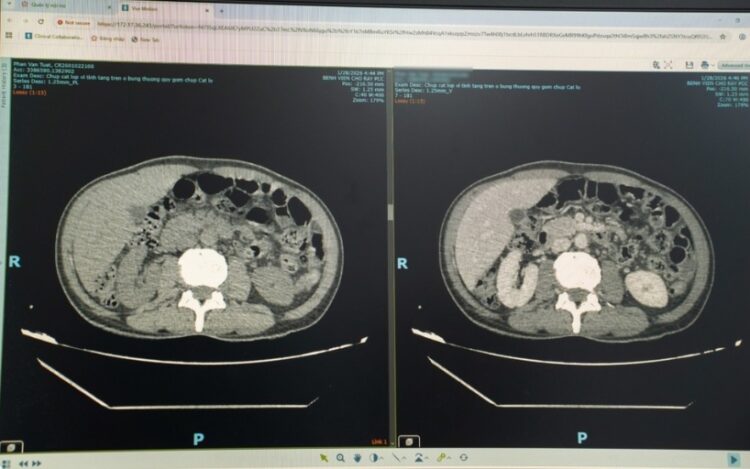

이 남성은 복부 초음파 검사를 받았고, 그 결과 간 농양이 발견됐다. 추가 검사와 정밀 영상 검사를 통해 간을 관통하는 6~7cm 길이의 이물질이 확인됐다. 의료진은 이물질로 인한 간 농양을 진단했다. 의료진은 "이물질이 체내로 들어가 소화관을 뚫고 간으로 이동해 국소 감염과 농양을 유발했다"고 설명했다.

의료진은 배를 열어 이물질을 수술로 제거했고, 농양을 배액했다. 간에서 나온 이물질은 대나무 이쑤시개였다. 수술 후 환자와 가족에게 물은 결과, 환자는 식후 이쑤시개를 입에 물고 있는 습관이 있다고 했다. 다만, 이쑤시개를 삼킨 기억은 없다고 했다.

의료진은 "이번 사례의 경우 농양이 간 깊숙한 곳에 있었고, 이물질이 횡격막과 주요 혈관에 인접해 있어 수술이 어려웠다"며 "원래 복강경 수술을 계획했지만 이물질 위치가 너무 깊어 배를 여는 수술을 해야 했다"고 했다. 이어 "그 결과 간 주변부에 위치한 간 농양을 제거하는 수술보다 수술 시간이 2배로 길었다"고 했다.